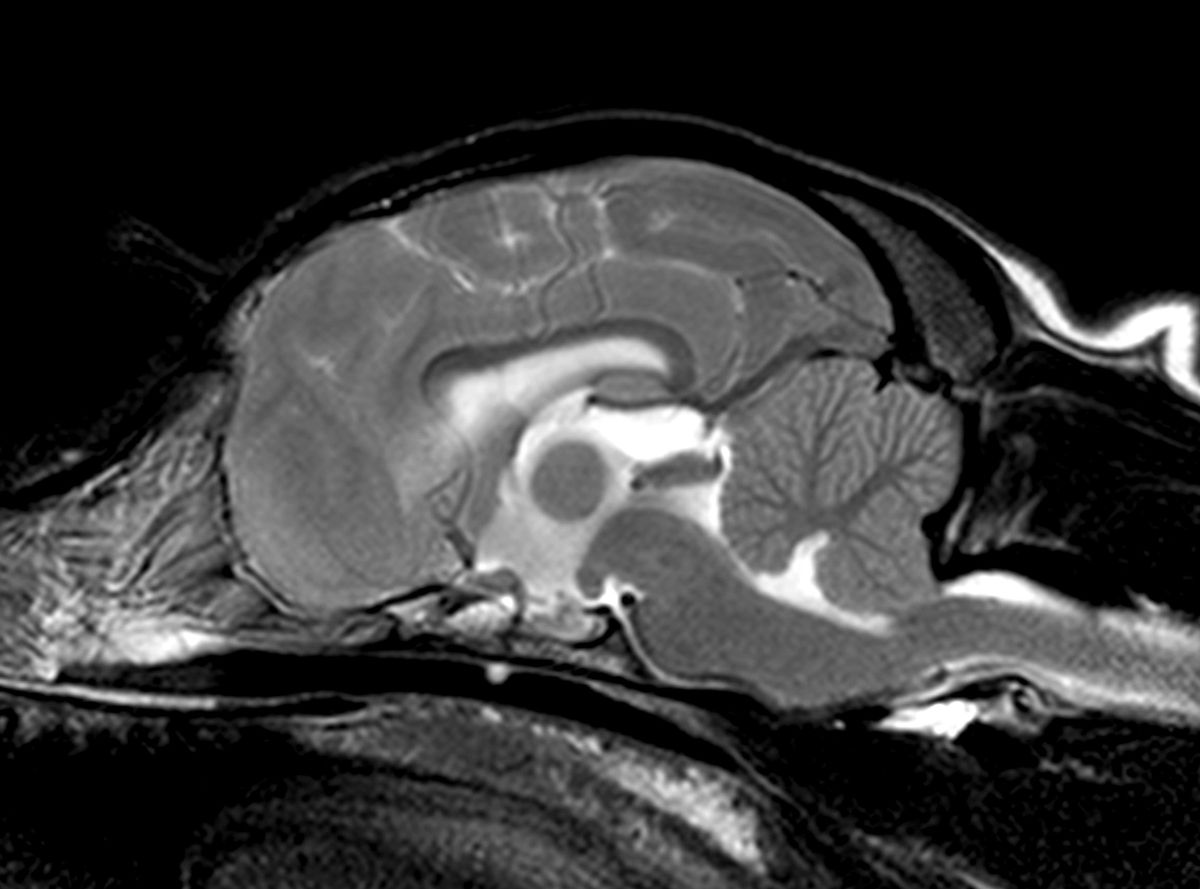

C'est un outil exceptionnel d'investigation non invasive d'une multitude d'organes ou zones, même si au départ son application principalement était dédiée à l'examen du cerveau et de la. Le scanner vétérinaire pour chien figure parmi les examens complémentaires qu'on pourrait vous demander L'imagerie par résonance magnétique ou IRM est une technique très largement utilisée en médecine humaine depuis de nombreuses années

Examen De Chien Sur Table Dans Une Clinique Vétérinaire à L'irm Soins Des Animaux Domestiques Ai. Il débute généralement les recherches de blessures ou de maladies avec des techniques plus classiques comme la radiographie ou l'échographie. Pourquoi passer un IRM ? Un examen IRM fournit une meilleure différence de contraste entre différents types de tissus qu'un examen par tomodensitométrie